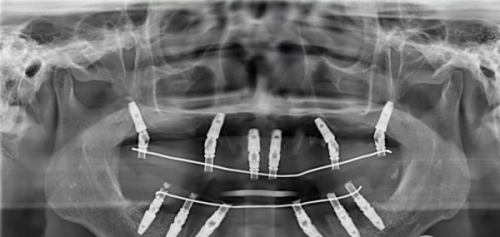

多颗及全口种植牙报价情况

多颗种植牙的价格主要与种植体数目和牙位数有关。需要种植的牙齿越多,费用自然也就越高。全口种植的价格跨度较大,在数十万之间,一般不超过50万元。

对于多颗牙缺失的患者,医生会根据具体的口腔情况制定个性化的种植方案。在这个过程中,种植体的数量和牙冠的选择都会影响更终的种植牙报价。全口种植牙是一项较为复杂的口腔修复项目,它不仅需要考虑种植体的稳定性和功能性,还需要关注美观度和舒适度。因此,全口种植牙的价格相对较高。